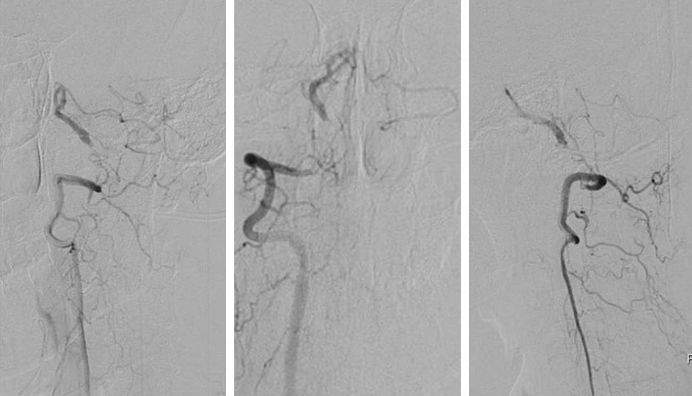

全麻下右股动脉入路, 将6F导引导管放至右椎动脉V2段远端,造影示右椎动脉V4段重度狭窄,狭窄率约为95%,狭窄长度13mm(图8)。

图8

路径图下沿导引导管送入Transend微导丝(0.014″,300cm)越过病变至基底动脉中段,沿微导丝送入Gateway球囊(2.75mm×15mm)于狭窄处预扩张(图9)。

图9

其后送入XT-27微导管,释放Neuroform EZ (4.0mm x 20mm )自膨式支架,造影提示支架释放后支架贴壁良好,前向血流TICI 3级(图10)。

图10